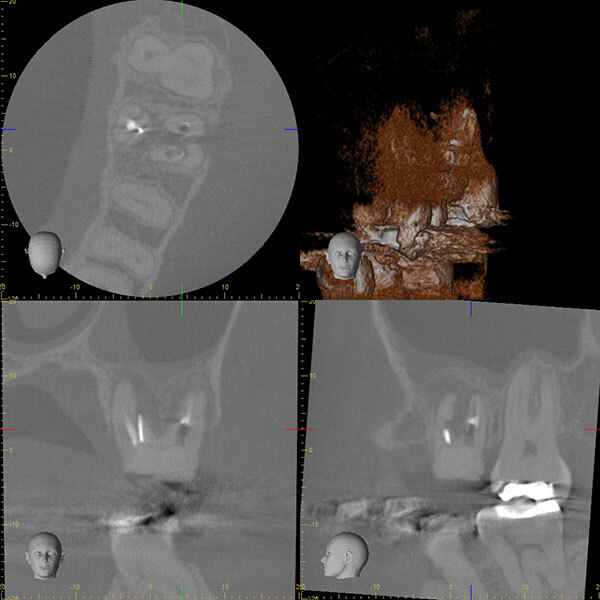

術前のレントゲン写真とCT画像と、お口の中の写真です。下の前歯2本(#31,41)です。

2本の根の周りに黒い影(透過像)があるのが分かります。

術直後のレントゲン写真です。

術後6ヵ月後のレントゲン写真とCT画像です。

術前にあった根の周りの黒い影は縮小して改善しているのが分かります。